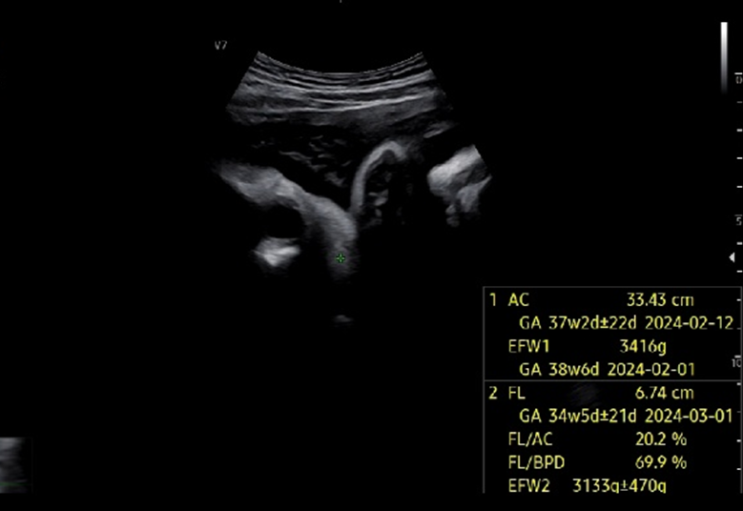

임신 38주차 제왕절개 출산 전 마지막 병원 진료

임신 38주차 제왕절개 출산 전 마지막 병원 진료 지금까지 병원은 무조건 토요일에만 방문했는데, 집에서 ...